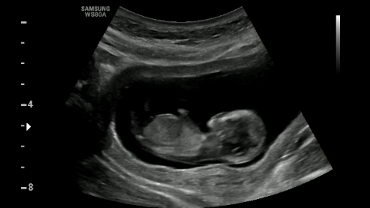

NT,英文Nuchal Translucency,即颈项透明层(蓝色区域)。NT超声检查是孕早期一项重要的超声筛查项目,主要用于评估胎儿染色体染色体异常(如唐氏综合征)或其他严重结构畸形的风险程度。

NT检查时间有严格规定

孕11周~13周+6天时进行

(即胎儿头臀长45~84mm)

超过此时期

颈项透明层可能逐渐消失

影响结果准确性